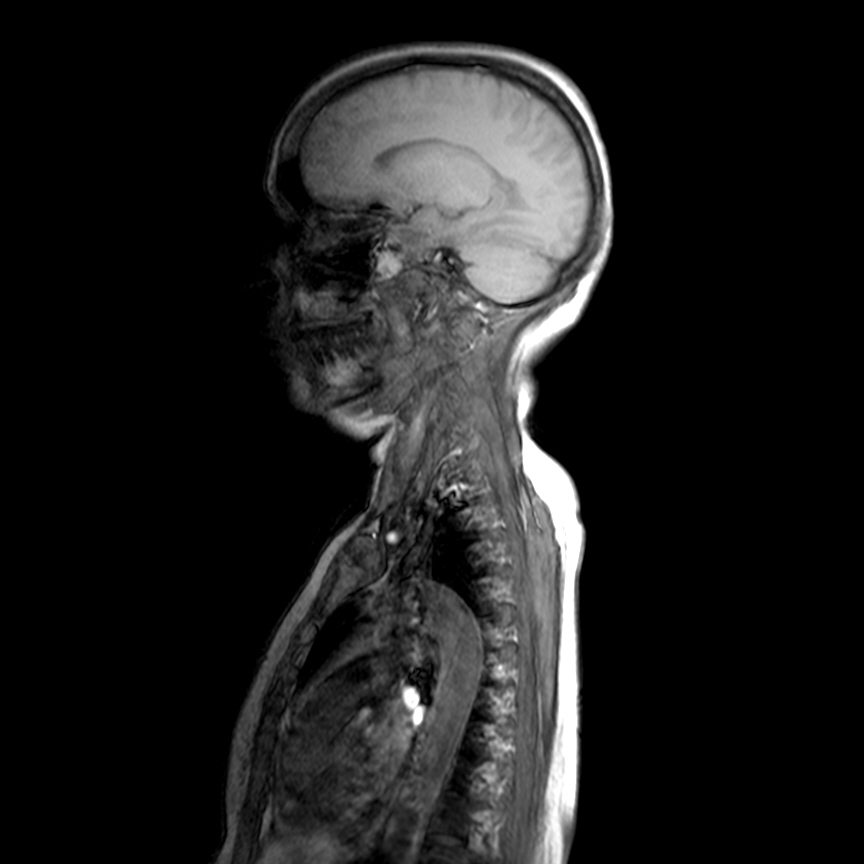

Needed help for this currently admitted 60 years old woman with gradual paralysis and severe back pain for the last few weeks. On examination there was slight gibbus and absent lower limb reflexes and MRI shows a lesion at L3 as well as T3.

Radiological images: